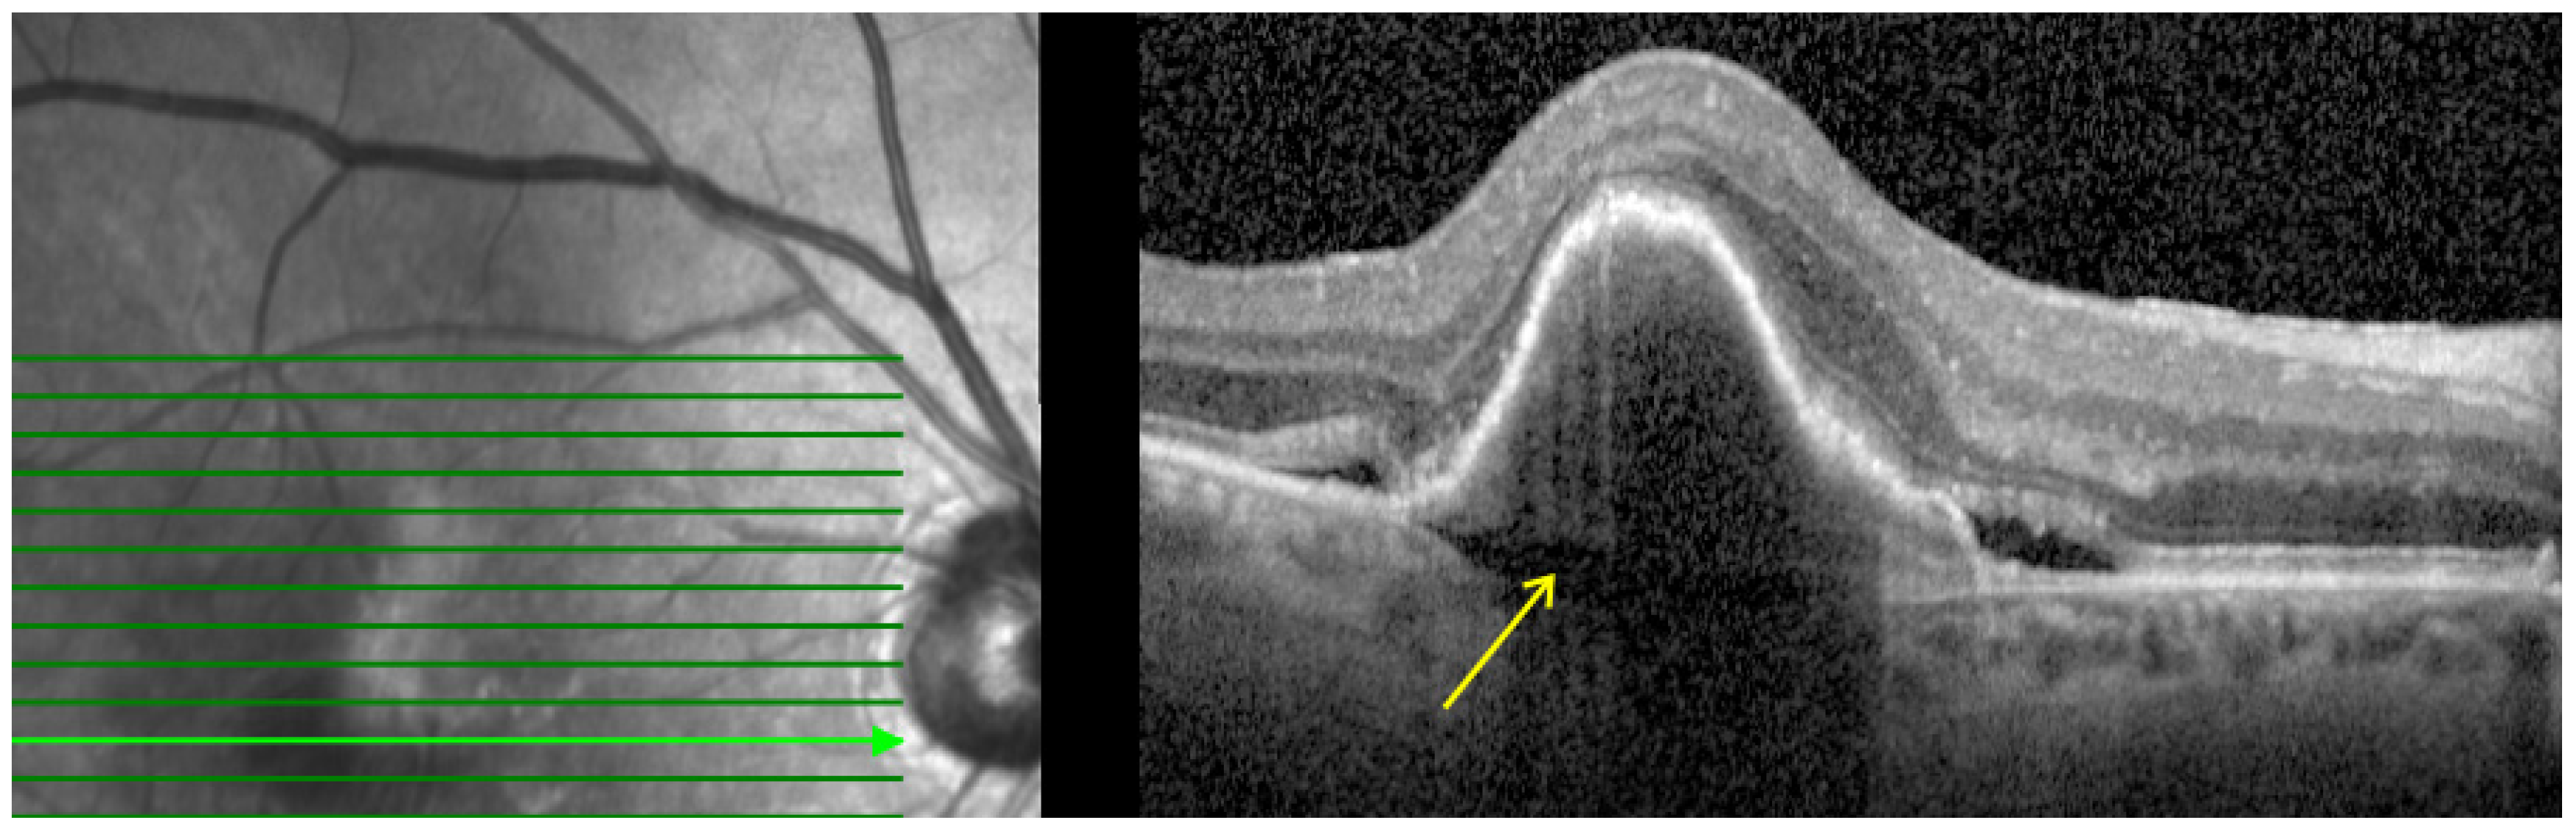

- Subretinal hyperreflective material (SHRM): Defined as a hyperreflective material located between the neurosensory retina and RPE as shown in Figure 3. In eyes with nAMD, SHRM is common and often persists after anti-VEGF treatment. SHRM is thought to have a negative impact on visual acuity and is likely to be composed of fluid, fibrin, blood, scar tissue, and MNV [29,30,31].